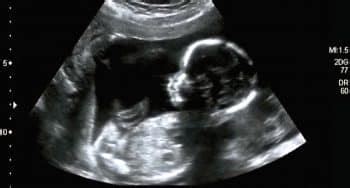

Echoscopie

Tijdens de echoscopie ligt de zwangere op een onderzoekstafel. Een professional gebruikt een apparaat dat, na aanbrengen van gel op de buik, geluidsgolven uitzendt die terugkaatsen van de foetus. Deze teruggekaatste golven worden omgezet in beelden op een monitor. Op basis van deze beelden, de grootte van de foetus en de analyse van de vrije ruimte, beoordeelt de arts de gezondheid van de baby.

- Eerste Trimester SEO (ETSEO): Dit onderzoek wordt uitgevoerd tussen de 11e en 14e week van de zwangerschap. Het wordt aangeboden binnen een wetenschappelijke studie (IMITAS) die de voor- en nadelen van dit vroege echoscopisch onderzoek onderzoekt. Bij 95% van de vrouwen worden geen afwijkingen gezien. Bij de overige 5% kan een mogelijk afwijking worden geconstateerd, waarna vervolgonderzoek wordt geadviseerd.

- 20-wekenecho (TTSEO): Dit is een uitgebreider echoscopisch onderzoek dat plaatsvindt tussen de 18e en 22e week van de zwangerschap. Het doel is het opsporen van lichamelijke afwijkingen bij de baby. Bij 95% van de vrouwen worden geen afwijkingen gezien. Bij 5% kan iets worden geconstateerd dat mogelijk een afwijking is, waarna verdere diagnostiek kan volgen.